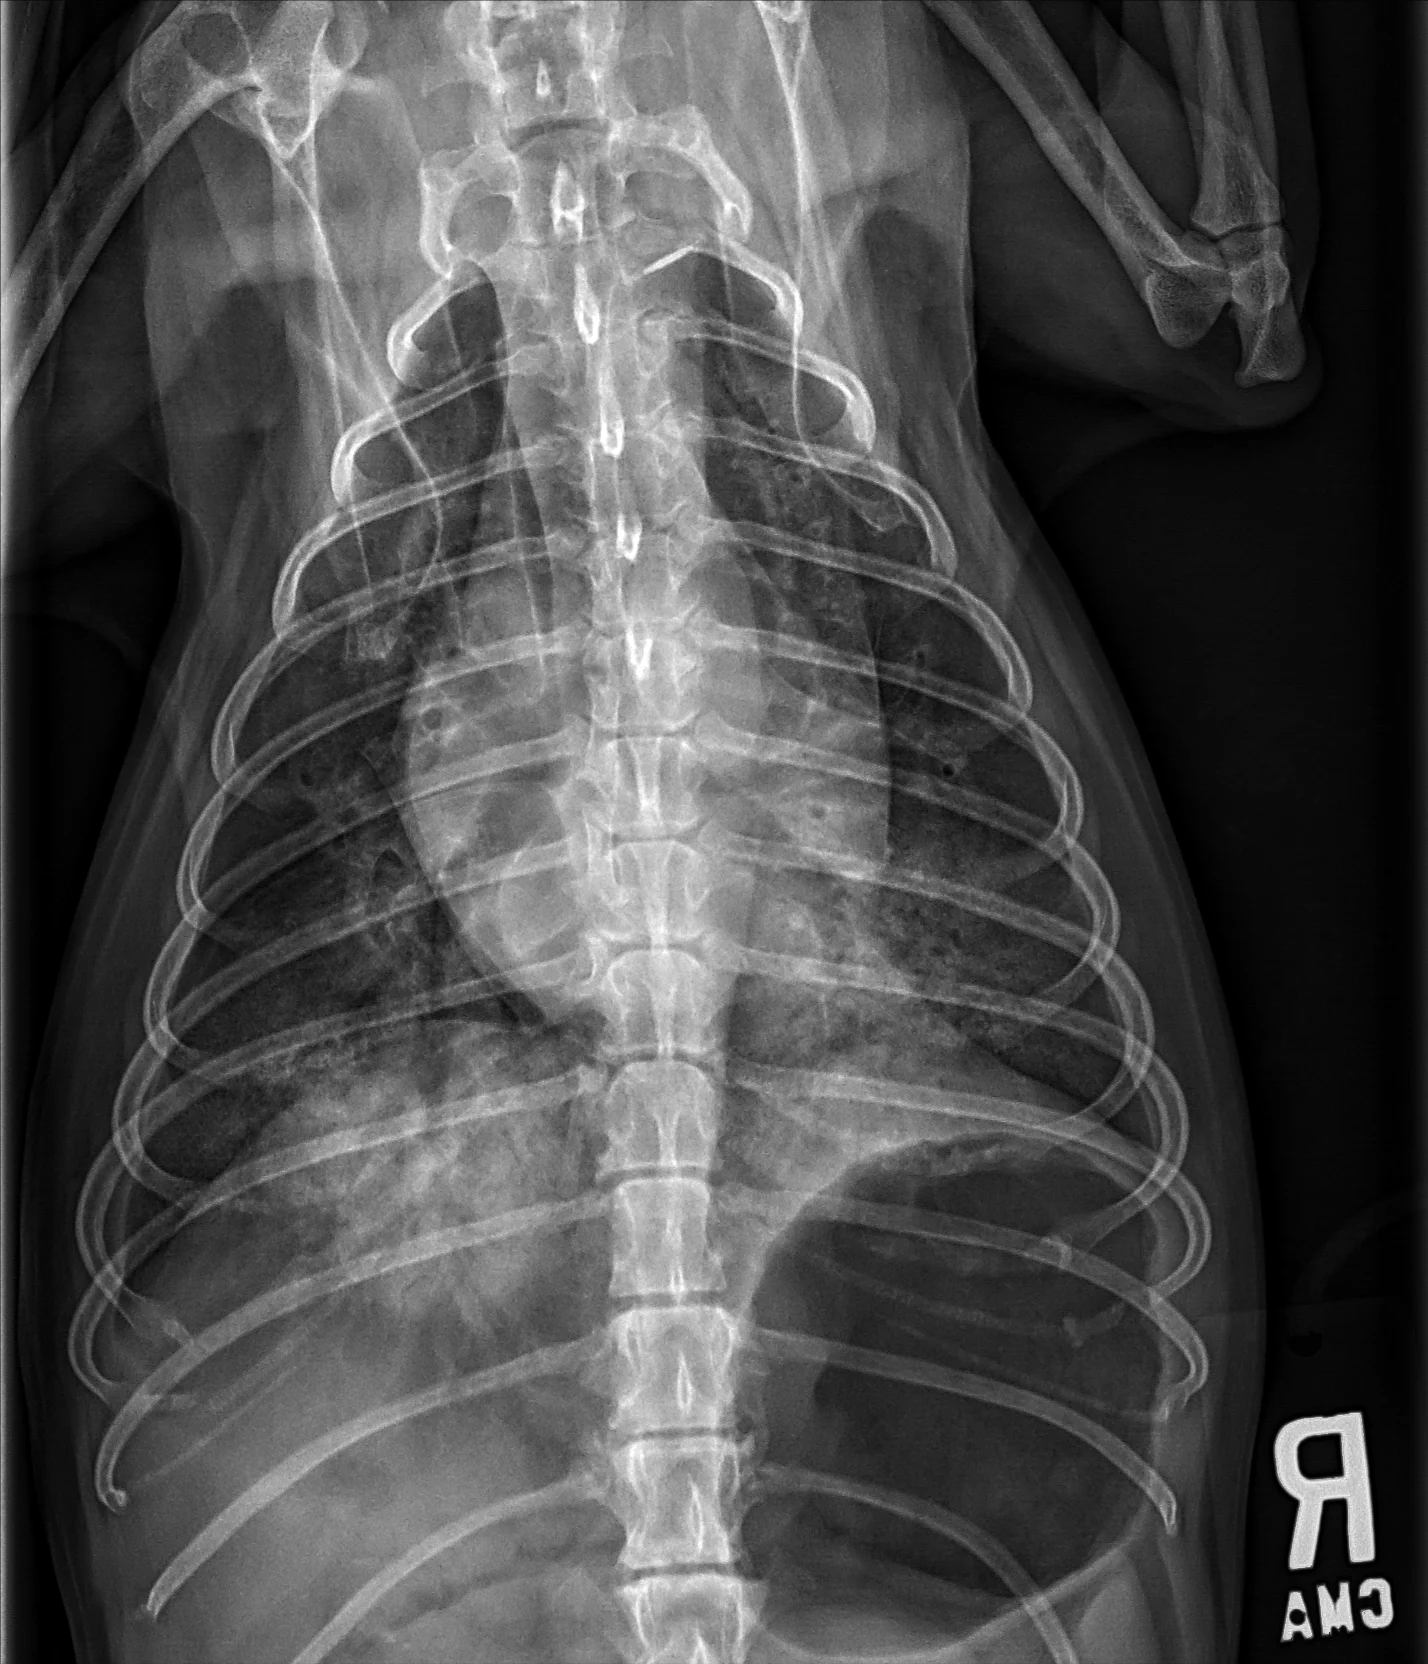

At least 2 orthogonal views, ideally taken during peak inspiration, are necessary for appropriate radiographic study of the cardiovascular system; however, a 3-view study is ideal for comprehensive evaluation of the thorax. Some differences should be considered when deciding to acquire a right versus left lateral projection and a dorsoventral (DV) versus ventrodorsal (VD) projection. On the left lateral view, the cardiac silhouette is typically more rounded and the apex is further elevated from the sternum than in the right lateral view (Figure 1). In the DV view, the cardiac silhouette is commonly displaced cranially and to the left by the diaphragm and appears more rounded than in the VD view. The caudal pulmonary vasculature is better delineated in the DV view, whereas the lung field (particularly the accessory lobe) is better evaluated in the VD view (Figure 2).

FIGURE 2 Normal DV (left) and VD (right) projections of the thorax in a large, crossbreed dog. The cardiac silhouette appears more rounded, and the caudal pulmonary vasculature is more apparent (arrowheads) in the DV view compared with the VD view. In some DV projections, the cardiac silhouette can appear significantly displaced to the left (not apparent in this case). Images courtesy of Federico Villaplana Grosso, DACVR, DECVR